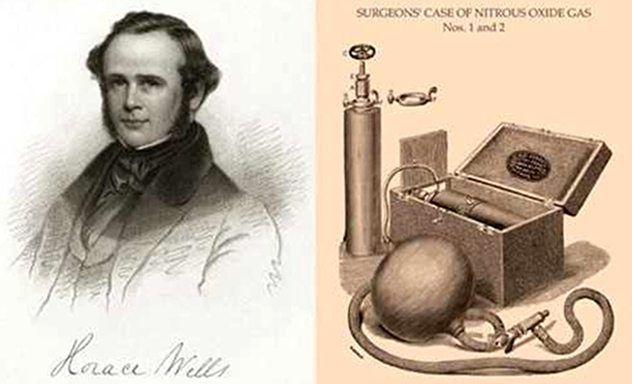

走进这家小店,你会被其独特的氛围所吸引,古朴的木门轻轻打开,迎面而来的是温馨舒适的环境,墙上挂着历代拔牙技术变迁的复古口腔医学挂画,温暖的灯光和专业的设备给人一种安心和信任的感觉,这里仿佛是一个隐藏在都市喧嚣中的秘密花园,让人心生好奇,想要一探究竟。

这家小店的拔牙技术是现代与传统完美结合的典范,他们不仅保留了传统拔牙技术的精髓,而且融入了现代科技的创新成果,你可以体验到传统拔牙技术的精湛技艺,更能感受到现代拔牙技术的神奇魅力。

现代拔牙技术强调无痛、微创、快速恢复,这家小店引进了国际先进的牙科设备,如数字化口腔扫描仪和三维口腔打印机等,为患者提供更加精准、个性化的诊疗方案,医生运用先进的麻醉技术,确保患者在无痛状态下接受手术,微创技术的应用大大减少了手术过程中的创伤,缩短了恢复时间。

这家隐藏在小巷中的特色小店是现代拔牙技术的一个缩影,这里你可以体验到国际先进的拔牙技术,感受到专业医生的关怀和温暖,如果你对现代口腔医疗技术感兴趣,不妨来这里一探究竟,相信你会有意想不到的收获,让我们共同关注口腔健康,关注现代拔牙技术的进展,迎接更美好的明天!